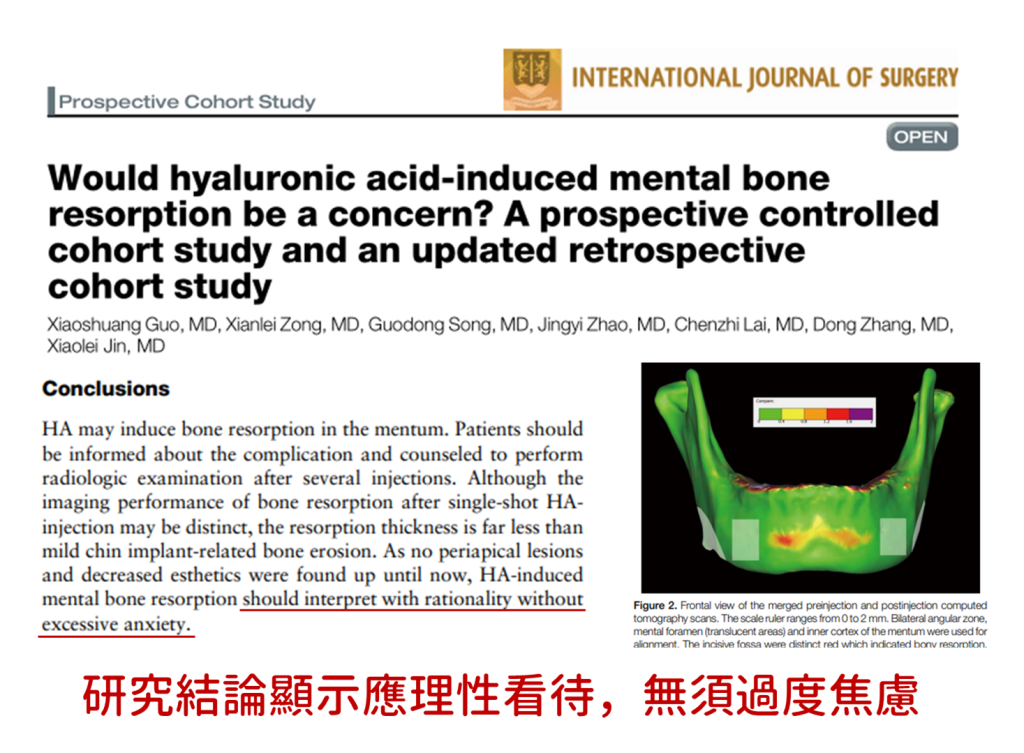

這場爭議源自一篇2024年的中國論文,研究團隊觀察78位曾接受玻尿酸下巴注射的患者,同時搭配2020年的回顧性分析,納入95位患者與95位對照者進行比較。由於研究發現部分受試者在影像中出現下巴骨質厚度減少、骨輪廓模糊等現象,學者因此提出注射玻尿酸可能與下巴骨質吸收有關的假設。此消息隨即在《小紅書》等平台發酵,甚至形成一股「玻尿酸吃骨頭」的恐慌,不少愛美民眾質疑:打玻尿酸真的會讓下巴後縮嗎?是不是注射愈多玻尿酸,骨頭就會愈空?

針對這些疑慮,楊仕安醫師澄清,玻尿酸為天然多醣體結構,能被人體自然吸收代謝,與骨骼組織並無直接交互作用,過往的醫學研究也從未將玻尿酸列為骨質疏鬆或骨質吸收的危險因子。此外,針對相關論文引起的爭議,義大利神經學與醫學影像專家 Dr. Roberto Dall’Acqua 也早已嚴正駁斥,表示將骨質變化單純歸咎於玻尿酸,忽視自然老化、假體壓力或顱顏骨骼的生理性重塑,是極不嚴謹且易誤導的論述方式。

實際從醫學角度來看,不少反駁論點也認為,跟玻尿酸相比,許多刺激組織再生的膠原蛋白增生劑,其引起的發炎反應更強,因此研究侷限於玻尿酸品類,在採樣上具有偏倚。更甚者,無論是假體還是填充劑,任何會造成「體積置換(volume displacement)」的植入物,理論上都可能對鄰近骨質造成壓力性吸收。就連原研究的作者也明確提到,相較於手術假體,玻尿酸所引發的下巴骨質變化幅度幾乎是微乎其微,並於結論明確顯示「無需過度擔憂」。

▲研究結論顯示無須過度擔憂骨吸收現象

此外,要判斷骨質是否因此流失,其實還有很多偽讀的誤區。楊仕安醫師解釋,影像上的變化並不等於實質上的臨床危害,像是CT或MRI影像可能因角度、解析度或玻尿酸的含水特性而看起來不同,也可能被誤認是骨頭變少。再加上每個人身體狀況、骨質條件、是否服藥(如類固醇)、甚至注射深度與技術都會影響影像呈現與後續反應。

再者,相關研究的樣本數過少,且使用的注射品牌、針具種類、注射層次與打法等關鍵變項相對侷限,因此不能輕易斷論玻尿酸會導致下巴外觀變形或結構崩壞。更矛盾的是,同一研究者的系列論文對於「多少劑量才會導致骨質流失」的結果竟前後不一致,顯示研究穩定性亦有待商榷。